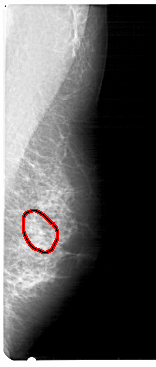

A_1388_1.RIGHT_MLO

RIGHT_CC LINES 4876 PIXELS_PER_LINE 1981 BITS_PER_PIXEL 12 RESOLUTION 43.5 OVERLAY

FILE: A_1388_1.RIGHT_MLO.OVERLAY

TOTAL_ABNORMALITIES 1

ABNORMALITY 1

LESION_TYPE MASS SHAPE ARCHITECTURAL_DISTORTION MARGINS ILL_DEFINED

ASSESSMENT 4

SUBTLETY 1

PATHOLOGY BENIGN

TOTAL_OUTLINES 1

BOUNDARY